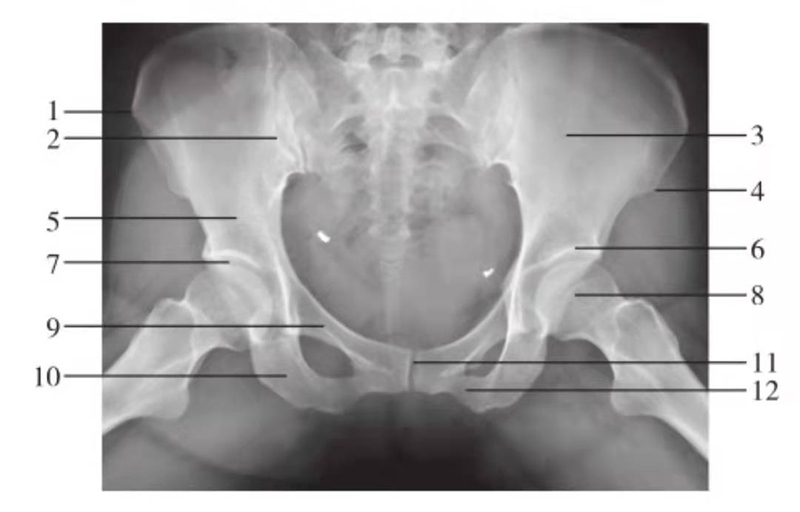

图6 骨盆正位

1.髂骨翼;2.骶髂关节;3.髂前下棘;4.髂骨体;5.髋臼顶;6.股骨头凹;7.股骨头;8.股骨颈;9.耻骨上支;10.大转子;11.坐骨支;12.耻骨联合;13.耻骨下支;14.小转子